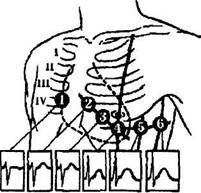

шлунків для ряду відведень; крапки реєстрації потенціалів зазначені на рис.3.

Крапки R, L і F, еквівалентні крапкам відведення по Ейтнховену

(права рука, ліва рука і ліва нога) у практичній електрокардіографії,

розташовувалися на торсі. Розташування інших крапок відведення було звичайним,

як прийнято в електрокардіографії. Були розраховані електрограми шлунків для 12

стандартних відведень, що зображені на рис. 3.

Рис. 3. Схема розташування крапок на поверхні тіла людини,

для яких розраховувалися потенціали зовнішнього полів шлунків у моделі

багатодипольного генератора серця.

Пунктирна лінія — частина контуру серця. Ключ До

замикається при вимірі ЕКГ у відведенні V4; а, б — вид попереду і

збоку (відповідно).

U — різниця потенціалів у відносних одиницях; t — час.